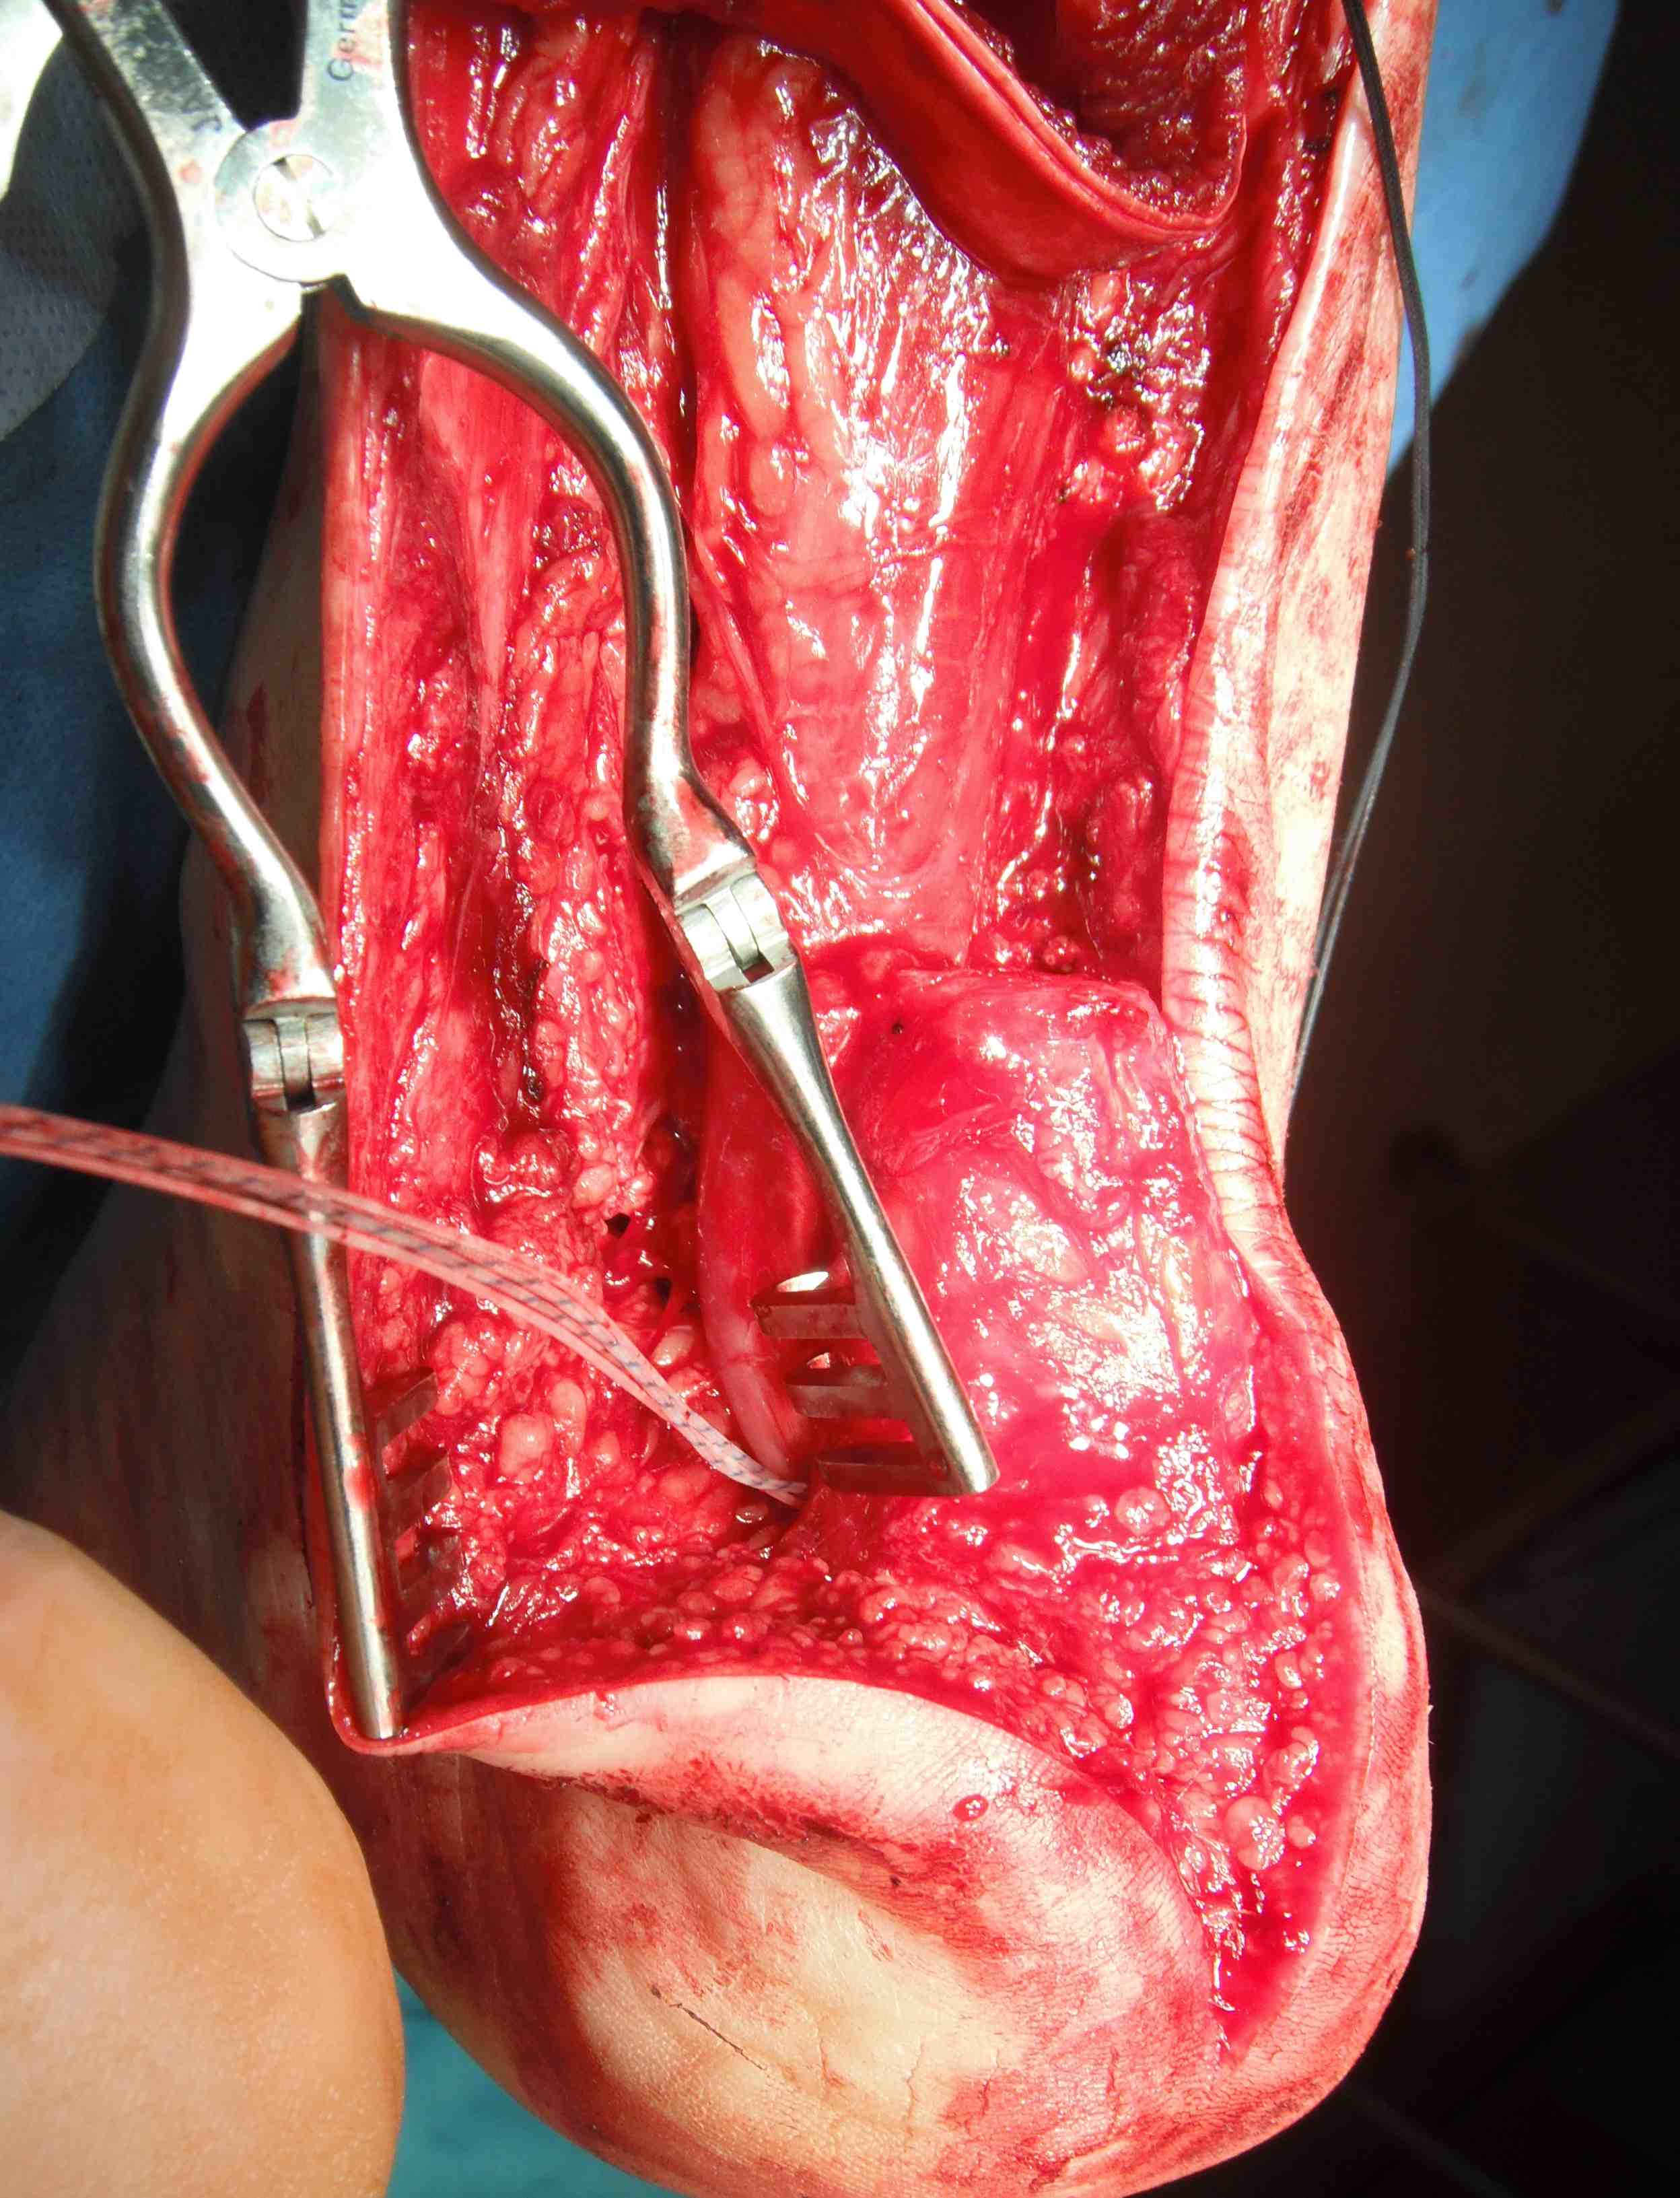

Turndown + FHL transfer with FHL passed through a transverse tunnel in the calcaneum

FHL transfer

Technique

Vumedi VY lengthening + FHL transfer video 1

Vumedi VY lengthening + FHL transfer video 2

Identify FHL tendon medially

- identify and protect tibial nerve

- pull tendon through and transect with sufficient length

- through drill hole in calcaneum and secure